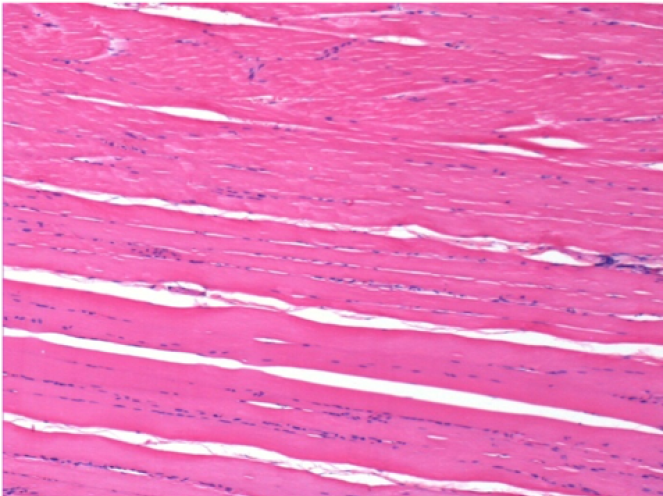

Controllo

Dopo iniezione di NaCl 0.5%

Commento : Niente da dichiarare dopo iniezione di soluzione fisiologica salina.

Sx:Pretibiale-Non trattato

Dx:Pretibiale-Dopo 0.1 ml NaCl 0.9% IM